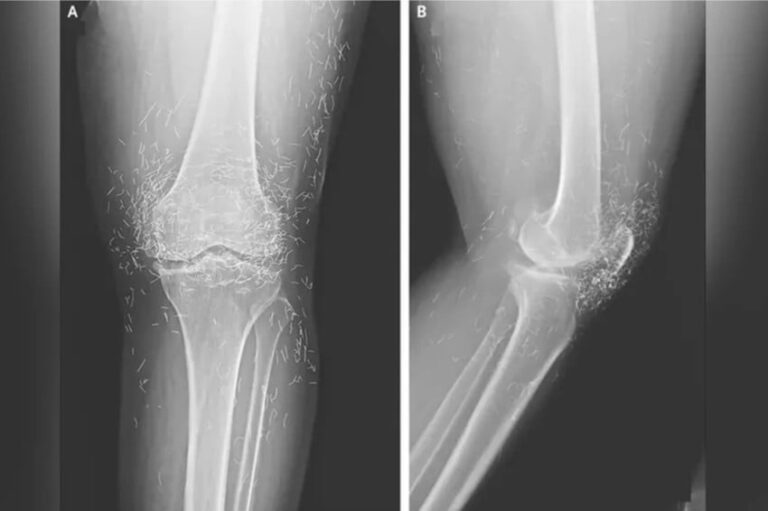

Viral! Dokter Temukan Ratusan Benang Emas Murni di Lutut Wanita Ini premanzone.biz.id Viral! Dokter Temukan Ratusan Benang Emas Murni di Lutut Wanita Ini admin September 18, 2025 0 loading… Sebuah peristiwa medis yang mengejutkan terjadi di Korea Selatan ketika tim dokter menemukan ratusan benang emas... Read More Read more about Viral! Dokter Temukan Ratusan Benang Emas Murni di Lutut Wanita Ini